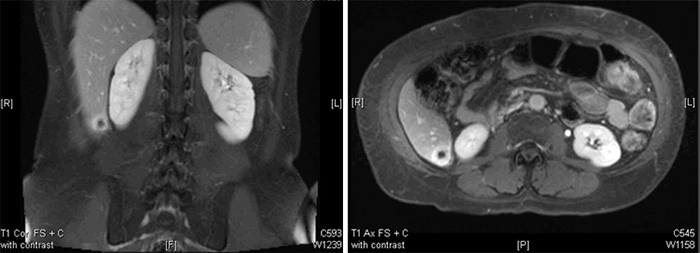

A MRI abdomen performed in July 2018 confirmed a segment six enhancing subcapsular lesion approximately 23 x 22 x 21 mm suspicious for a primary liver malignancy such as hepatocellular carcinoma or a hepatic metastasis (Figure 2).

Figure 2. MRI of patient showing segment six ring enhancing mass.